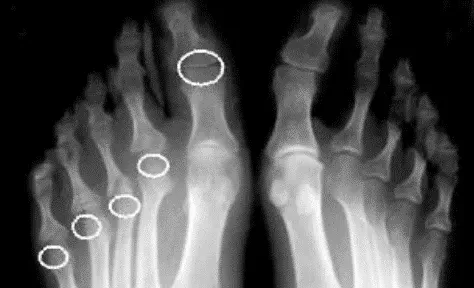

Рисунок 12. Рентгенограмма стоп при псориатическом артрите. Асимметричный эрозивный артрит с остеолизом ПлФС правой стопы и внесуставная эрозия 1-го межфалангового сустава

3Характерные рентгенологические изменения при псориатическом артрите: сужение суставной щели; костная ремодуляция (резорбция концевых фаланг, крупные эксцентрические эрозии, остеолиз – деформация «карандаш в стакане») и пролиферации (краевые костные разрастания, периоститы, энтезофиты и костные анкилозы), асимметричный двусторонний/односторонний сакроилиит, паравертебральные оссификаты и краевые синдесмофиты